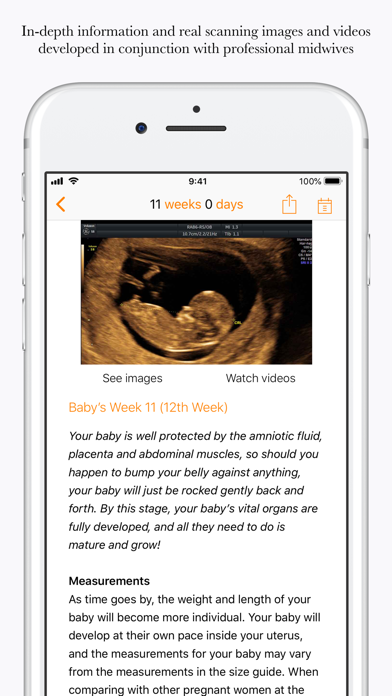

Your pregnancy - Day by Day

Скриншоты